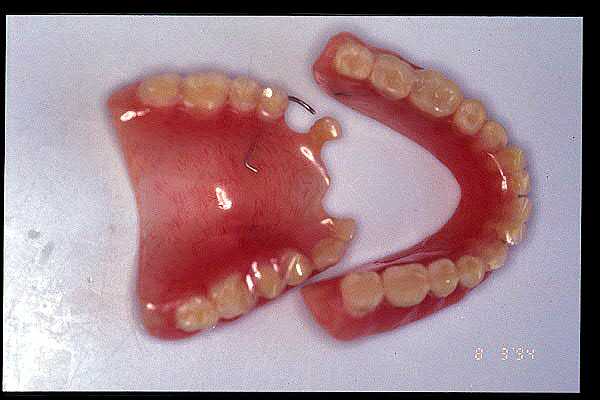

CM Prótesis del año 1950